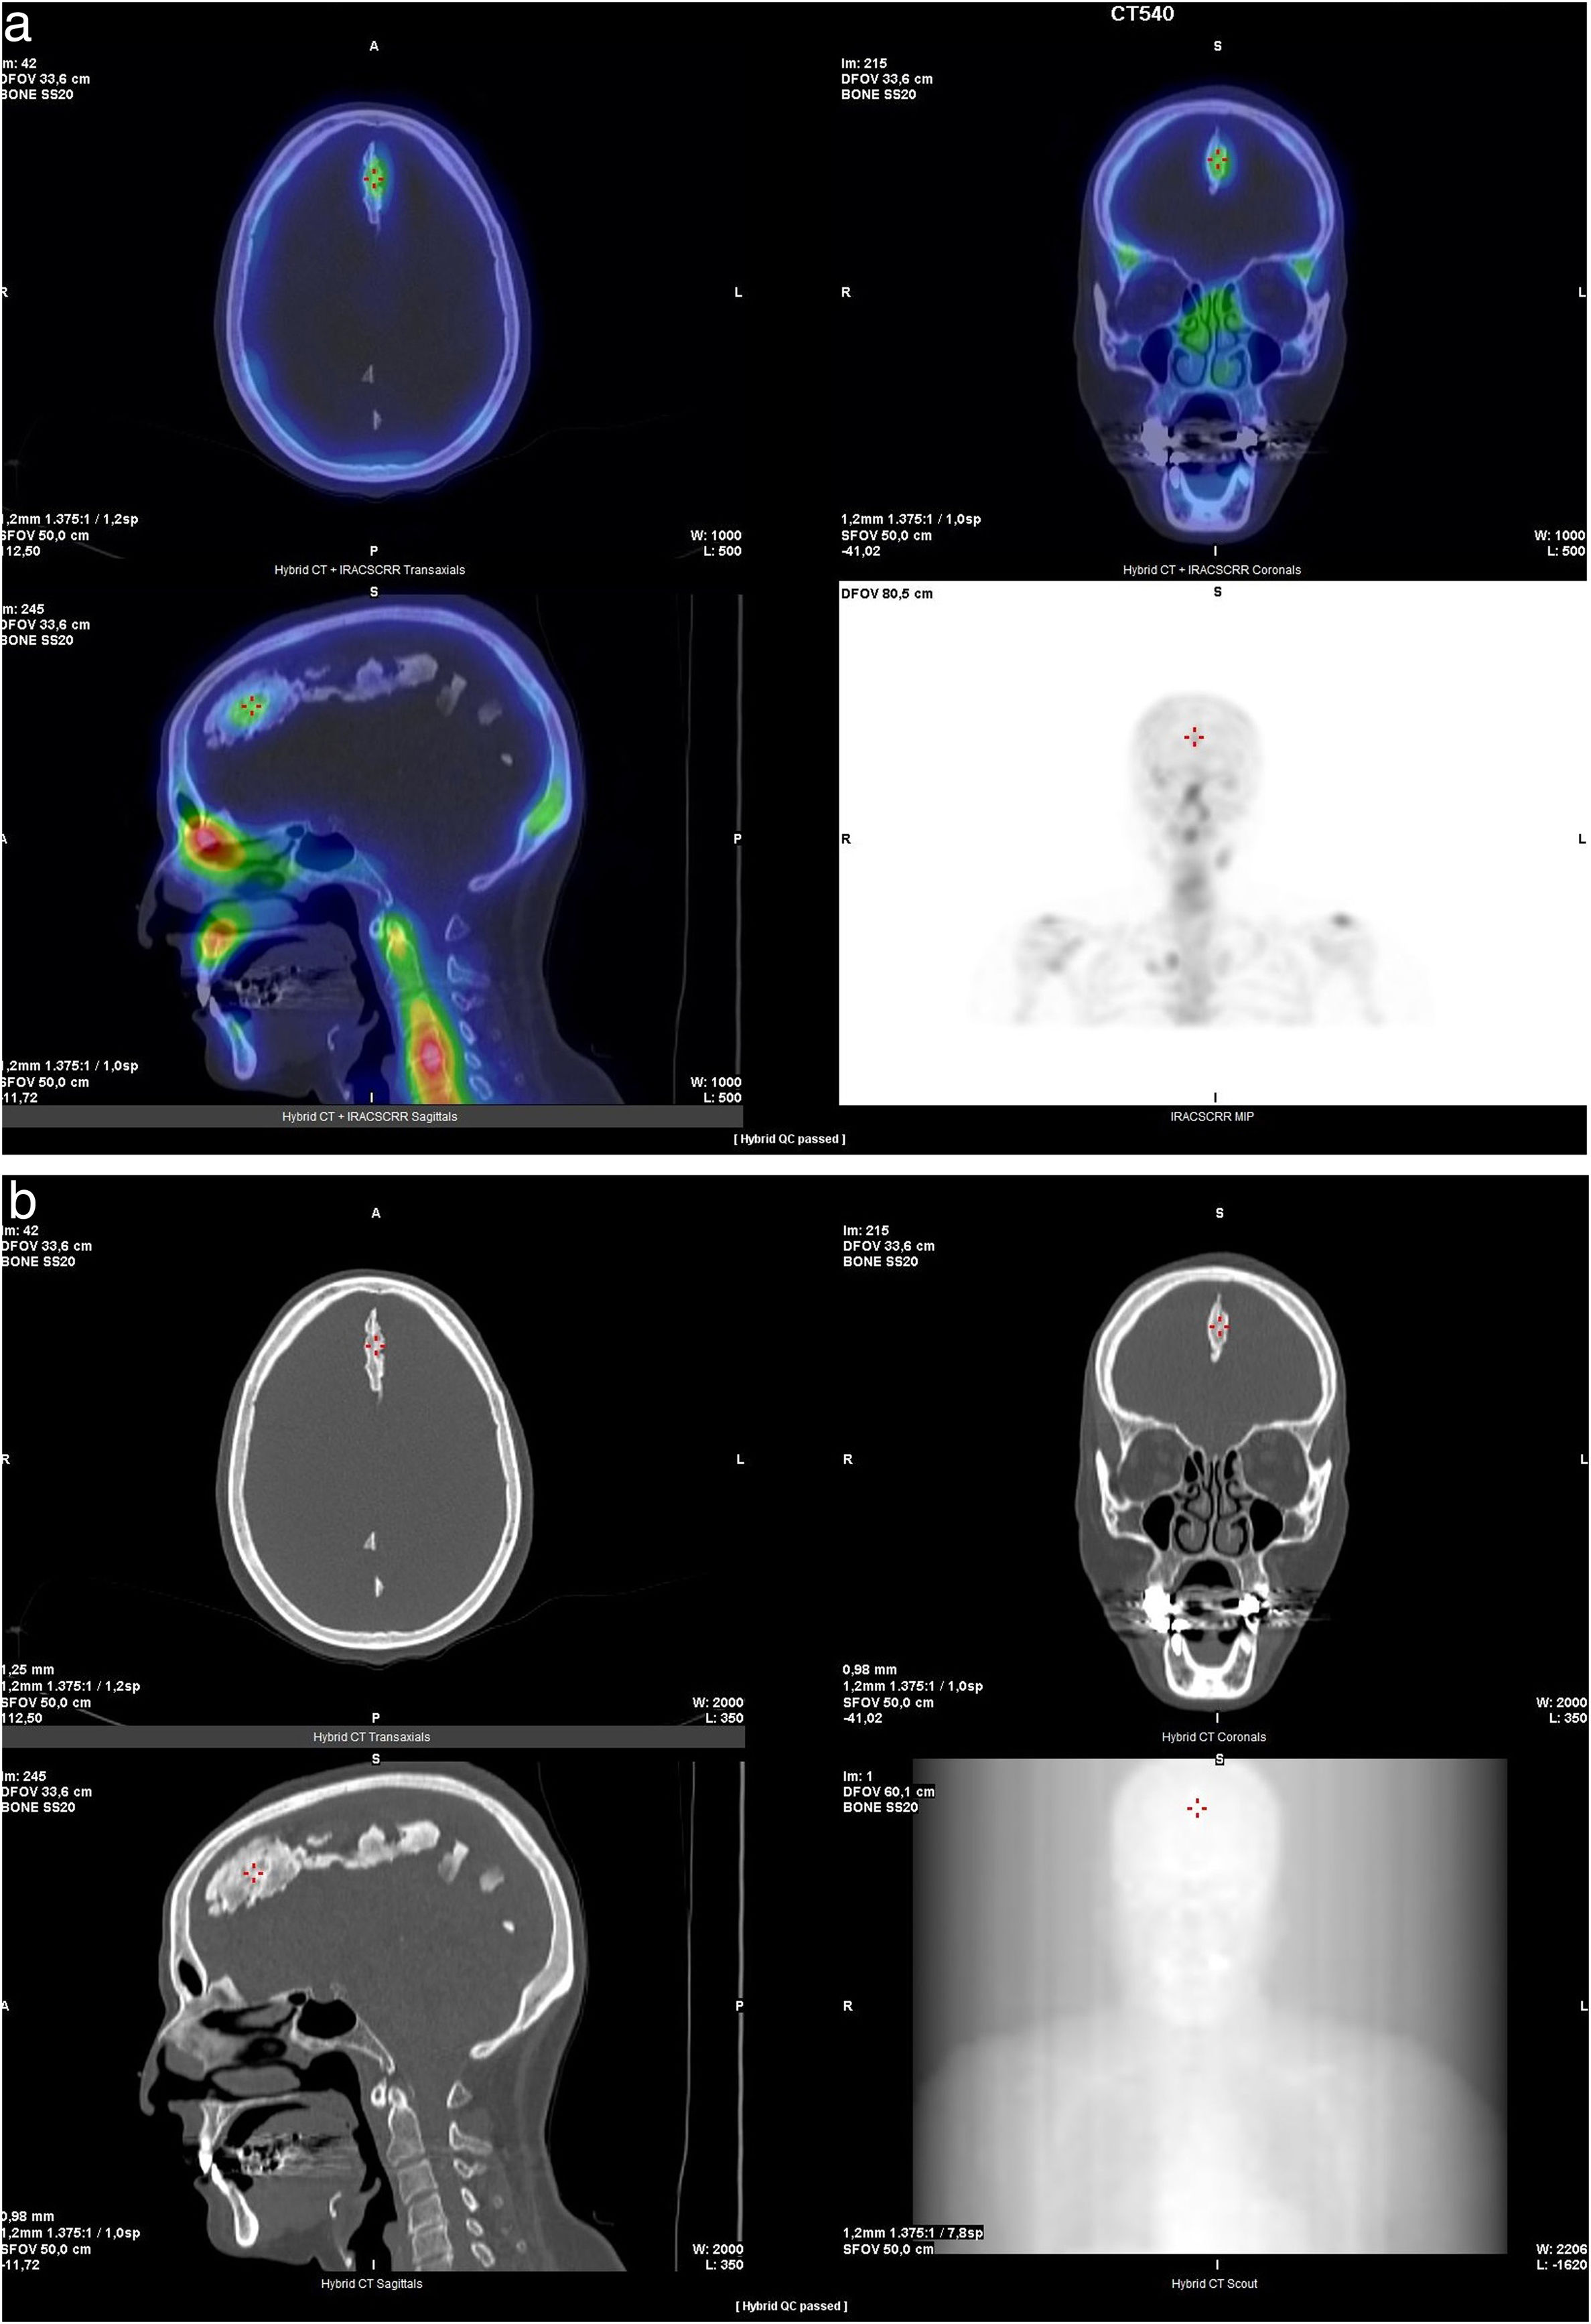

Revista Española de Medicina Nuclear e Imagen Molecular (English Edition) Ossification of the falx cerebri in a patient with metastatic breast cancer

Ossification of the falx cerebri in a patient with metastatic breast cancer

Osificación de la hoz del cerebro en cáncer de mama metastásico